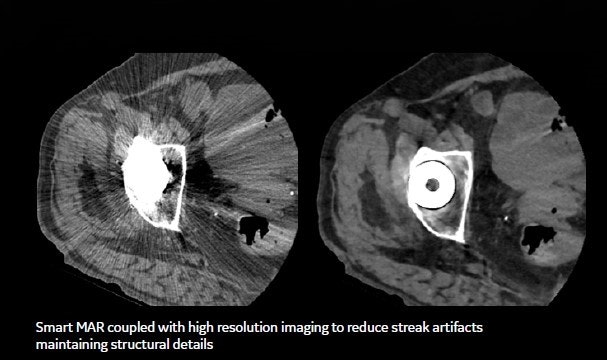

A Smart MAR, (single acquisition metal artifact reduction) image, reduces metal streaking caused by hip replacements and other metal in the body to visualize soft tissue around the joint that we could not see before.